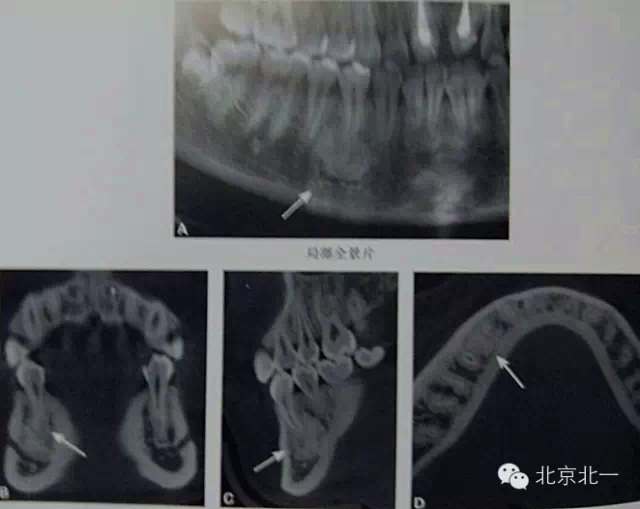

【CBCT表現(xiàn)】:

牙骨質(zhì)增生可表現(xiàn)為整個牙根體積的膨大,或僅表現(xiàn)為根尖呈球狀增生,對于多根牙,體積的膨大可局限于個別牙根,不伴根尖周感染的情況下,便便牙牙周膜及硬骨板影像相連續(xù)、完整。部分病例可見牙周膜間隙消失,牙根與牙槽骨粘連,導(dǎo)致牙齒萌出障礙或者滯留。

B6腭根根尖區(qū)膨大,牙周膜和骨硬板消失,根尖周見低密度影,上頜竇下壁骨質(zhì)不連續(xù),B B6頜面已開髓。

在CBCT上,根尖型骨島無低密度帶狀影包繞,與周圍骨質(zhì)分界清晰,具有特征性的毛刷樣邊緣,且其發(fā)生區(qū)域的牙根牙周膜影像連續(xù)、完整、不導(dǎo)致頜骨的膨隆。

右下頜C4根尖區(qū)課件一類圓形高密度影,與周圍骨質(zhì)分界清晰,C4牙周膜影像連續(xù)、完整,下頜骨未見膨隆。